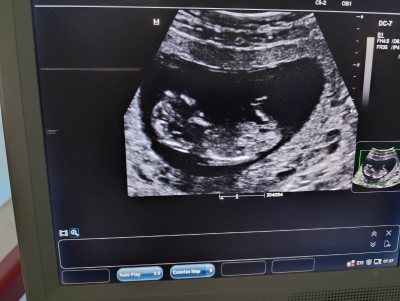

Cinsiyet tahmini yaparmisiniz anlayanlar bakabilirmi

Gebelik haftası 12

Bende 12 haftalıgım çok merak ediyorum seninki sanki erkek gibi geldi bana doktorun tahmin etmedi mi

Çıkıntısı yok kız gbi cnm

Erkek bebeklerde bacak arasında çıkıntı oluyor kizlarda boş 3 çizgi oluyor

Kafa yapısı erkege benzıyor sankı suan benım ıkıncı gebelıgım oglumun kafa yapısıda bu sekıldeydı kızlarda genelde yuvarlar erkeklerde daha oval oluyor ama cıkıntı falan pek anlamıyorum bende hakkında hayırlısı olsun

Kıza benziyor canım hayırlısı olsun